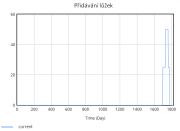

| 22:34, 15 June 2025 | 1 PřidáváníLůžek.png (file) |  |

7 KB | Kozo01 | 1 | |